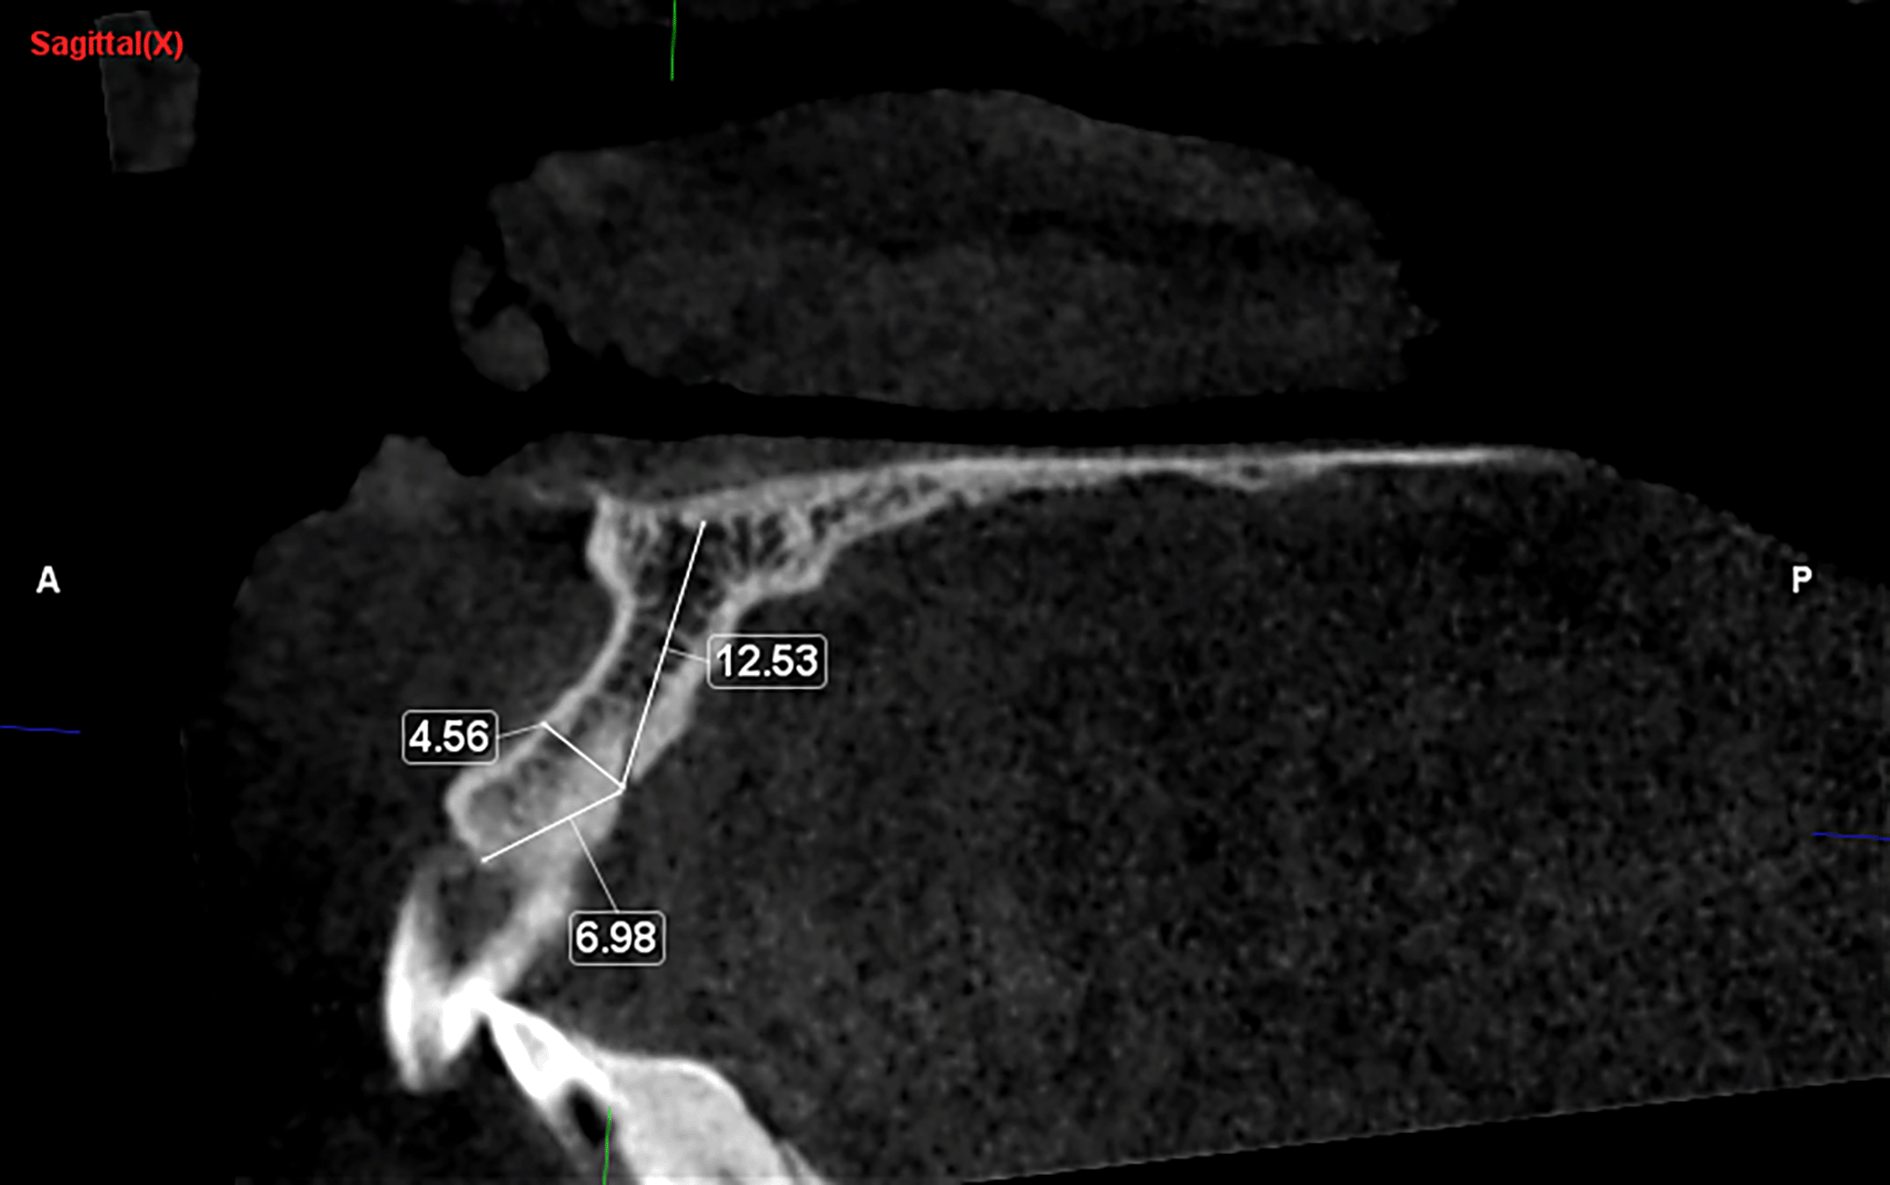

Distance of CS from cortical plates, alveolar crest and nasal floor ( Figure 3)

The mean diameter of the CS near the alveolar crest was measured at 0.76 mm (±0.27) on the left side and 0.80 mm (±0.27) on the right side. The distance from the CS to the alveolar crest was recorded as 9.23 mm (±3.58) on the left side and 9.22 mm (±3.39) on the right side. The distance from the CS to the buccal cortical plate was 7.19 cm (±1.65), with a median of 7.18 cm, on the left side and 6.82 cm (±1.74) on the right side. Additionally, the distance from the CS to the floor of the nasal cavity was 11.4 cm (±3.78) on the left side and 11.6 cm (±3.64) on the right side ( Figure 5).

Distance from Adjacent Structures: In our study, the distance measured from the CS to the alveolar crest was slightly over 9 mm, closely aligning with the findings of Manhães et al.2 In contrast, Gürler et al. reported a significantly greater distance of 16.81 mm.18 Meanwhile, Samunahmetoğlu E. and Kurt MH5 found a distance of 7.71 mm, and Beyzade Z et al.16 reported 5.87 mm, both slightly less than our result. The distance from the CS to the buccal cortical plate was over 7 mm, consistent with the findings of Manhães et al.2 However, Beyzade Z16 and Samunahmetoğlu, E. and Kurt, M.H.5 found it to be less than 5 mm in their study. In our study, the distance measured between the CS and the nasal cavity exceeded 11.4 mm, aligning with the observations reported by Manhães et al.2